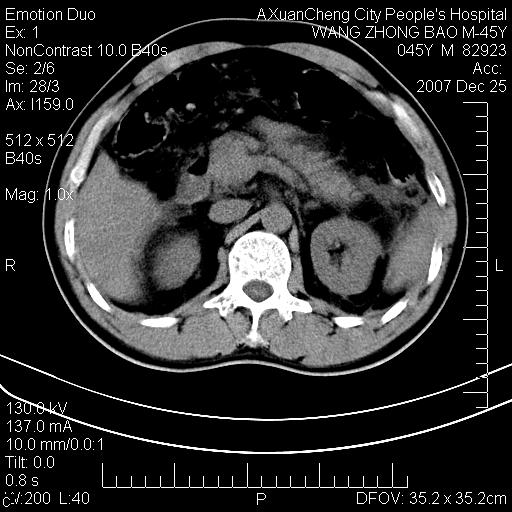

以下是引用卜一在2007-12-25 14:07:00的发言:[br]胰头钩部略增大,与十二指肠壶腹部关系密切,其内明显见软组织密度肿块,明显强化,但肠壁较光滑 柔软。考虑:炎性增生!建议消炎后复查!待除外壶腹部腺癌!

以下是引用zjzjr在2007-12-25 13:35:00的发言:[br]考虑正常的十二指肠乳头部,建议胃镜检查.

以下是引用qiuleiyu在2007-12-25 18:14:00的发言:[br]胰腺增大,周边渗出改变,肾前筋膜明显增厚,示少量积液.胆囊壁毛糙,周边少许渗出,胆总管壁厚,异常强化,然扩张不明显.结合病程急短;考虑;胆管炎,胆囊炎,胆源性胰腺炎可能大,请结合实验室检查及随访.

以下是引用lisihao在2007-12-25 14:23:00的发言:[br]急性水肿型胰腺炎[br]依据:1、胰腺弥漫性肿大,边缘稍毛糙;[br] 2、双侧肾周筋膜增厚,尤以左侧为甚(重要征象)[br] 3、双侧后胸膜增厚(刺激性炎症);[br] 4、结合病史,查血尿淀粉酶应该可以确诊。